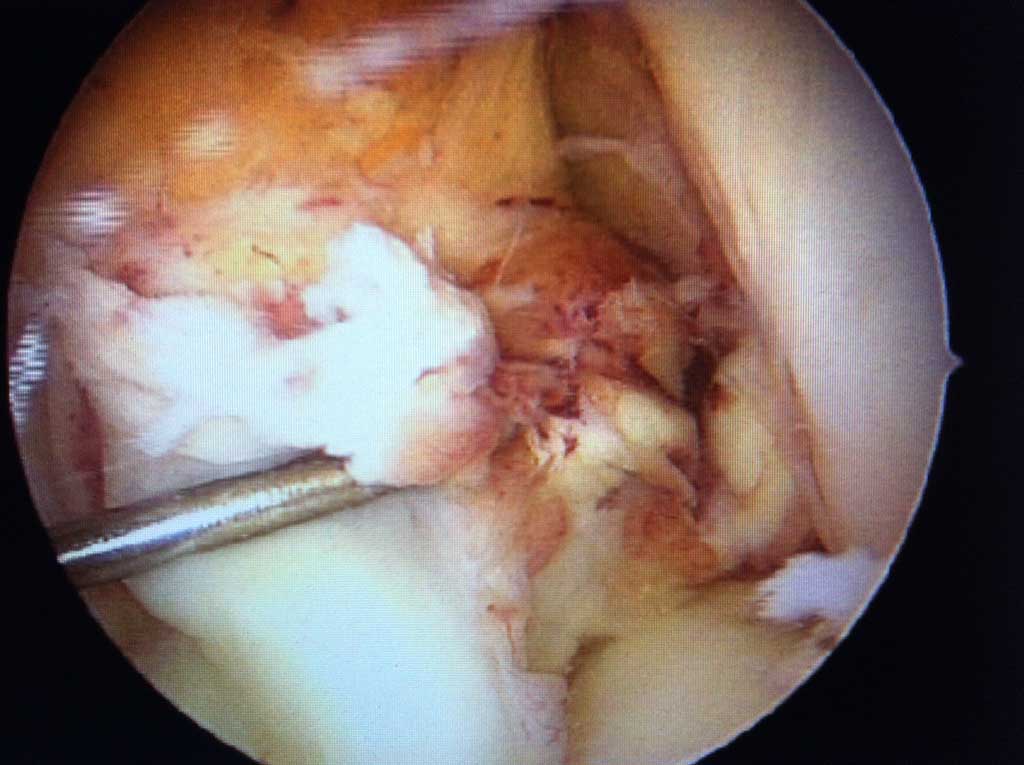

Arthroskopische Microfracturierung

Wie läuft die Operation ab?

Bei gut abgegrenzten Knorpelschaden bis zur 2,5 cm2 Grösse wird im Rahmen einer ambulanten arthroskopischen Operation der frei liegender harter Knochen auf dem Boden des Knorpeldefektes an mehreren Stellen perforiert ( " eingebrochen " = fracture ). Aus diesen Öffnungen kommt es zur Einblutung des Knorpeldefektes und aus dem Blutgerinsel ( Koagel ) entsteht innerhalb von 6-10 Wochen ein Knorpelregenerat ( "Knorpelnarbe") Die OP Dauer beträgt in Spinalanästhesie 15-30 Minuten.

Knorpel-Knochen Übertragung ( OATS, "Mosaikplastik")

Wie läuft die Operation ab ?

Dieser knorpelwiederherstellender Eingriff wird bei geeignetem isolierten, eher kleineren Knorpelschaden entweder arthroskopisch oder "mini open" unter stationären Bedingungen durchgeführt. Es werden dabei aus einem minimal belasteten Areal des betroffenen Kniegelenkes ein oder mehrere Knorpel-Knochen Zylinder entnommen und diese dann in " press fit " Technik in den speziell vorbereiteten Knorpeldefekt in der Belastungszone übertragen. Die Einheilung ist im wesentlichen in 6-8 Wochen abgeschlossen ( Knochen - Knochen Heilung ) und in dem Defekt befindet sich ein original Gelenkknorpel. Die Entnahmestellen füllen sich mit Faserknorpelgewebe.

Diese Operationstechnik verlangt eine sehr große Erfahrung des Operateurs und sollte daher nur durch Kniespezialisten mit Expertise in der gelenkerhaltenden Chirurgie durchgeführt werden!